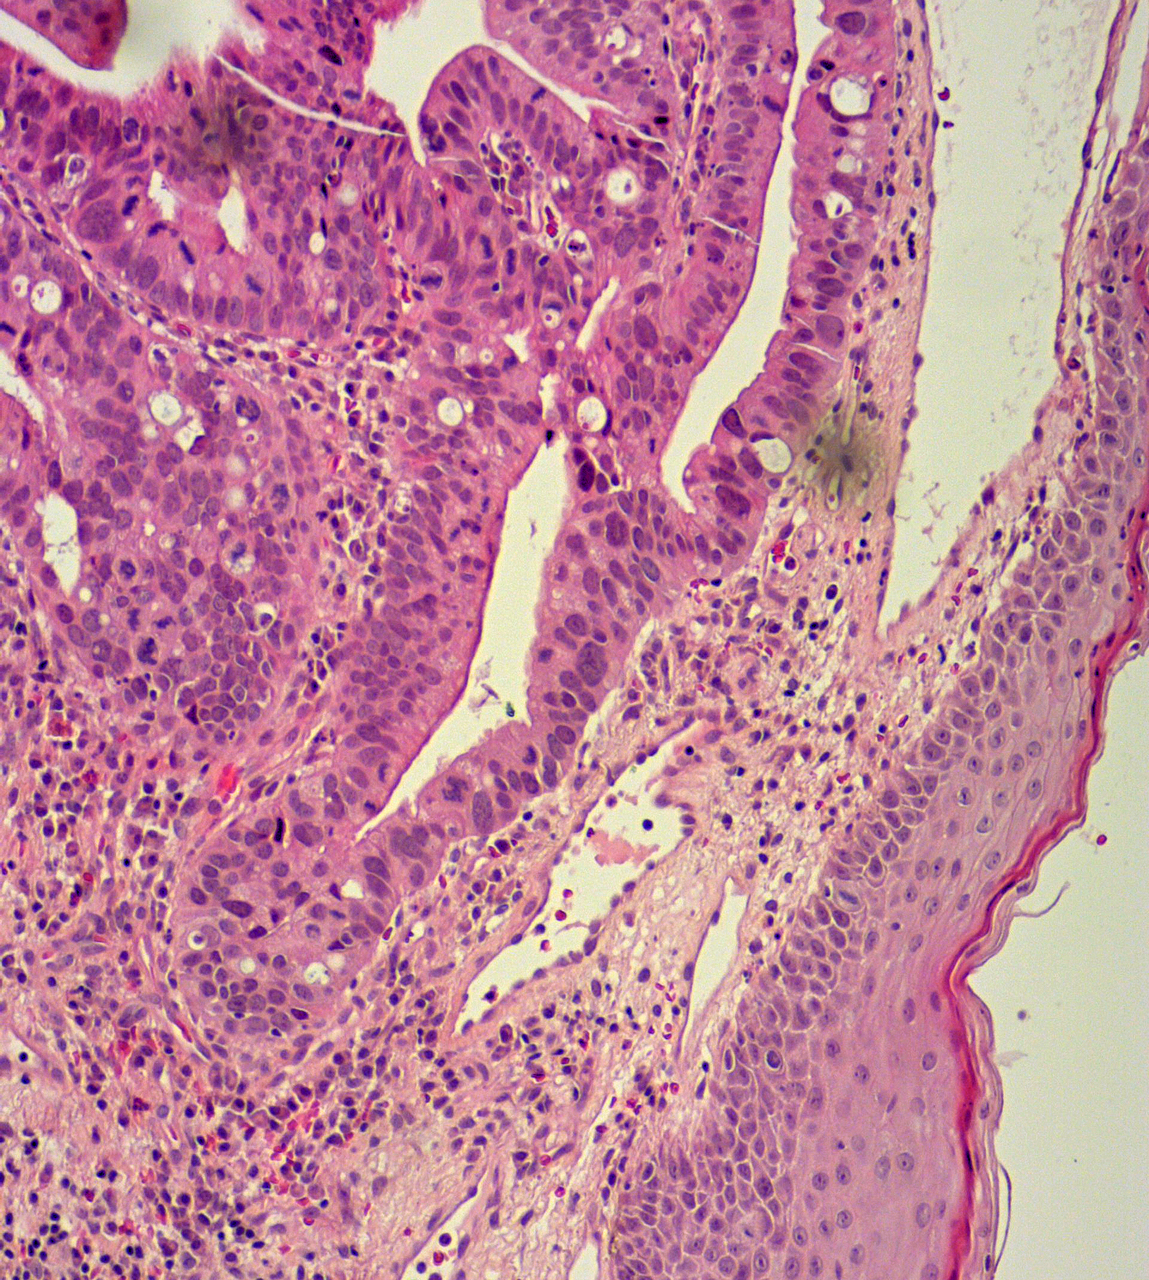

L’examen clinique met en évidence un nodule induré au niveau de la marge anale (fig. 1).

La symptomatologie est non spécifique. Il peut s’agir d’une sensation de boule, de douleurs, de saignements, de suintements, etc. L’examen clinique peut révéler une lésion bourgeonnante et/ou ulcérée, mais aussi une fistule, voire des papules érythémateuses plus ou moins kératosiques en cas de maladie de Paget.

Les principaux diagnostics différentiels sont la thrombose hémorroïdaire externe, le prolapsus hémorroïdaire -interne, la marisque hypertrophique et le carcinome épidermoïde en cas de nodule. En cas de maladie de Paget, ce sont le psoriasis, les mycoses, l’eczéma de contact, les -dermites d’irritation, le lichen plan ou scléro-atrophique et la  maladie de Bowen. Le diagnostic formel nécessite une analyse histologique (fig. 2).